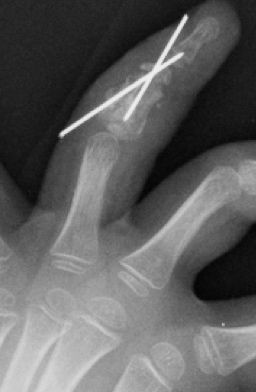

Se debe evitar atravesar la superficie articular con las agujas y utilizar agujas de diámetro adecuado para evitar secuelas, aunque en ocasiones es imposible sintetizarlas sin atravesar la articulación (Figura 24).

Figura 24: a- Fractura del cuello de falange media con desplazamiento posterior que requiere tratamiento quirúrgico. b- Reducción cerrada y estabilización con agujas de Kirschner.